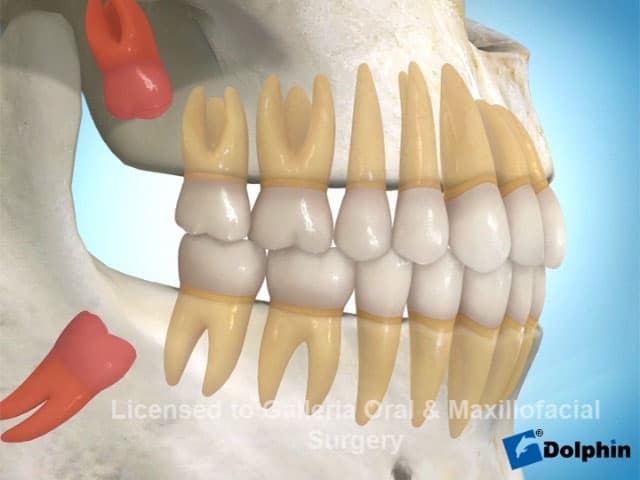

Receive a complete set of permanent teeth in a single visit with our All-on-4 and All-on-6 immediate-load implant protocols. Dr. Antipov uses 3D cone beam CT imaging and computer-guided surgical templates for precise, predictable placement — even for patients who have been told they don't have enough bone. For severe upper jaw bone loss, we offer zygomatic implants anchored to the cheekbone, eliminating the need for extensive bone grafting. Every full arch case includes same-day temporary teeth so you never leave without a smile.

Single & Multiple Tooth Implants

Whether you are missing one tooth or several, dental implants provide the most natural and durable replacement available. Dr. Antipov places single tooth implants with immediate temporary crowns, implant-supported bridges to replace multiple adjacent teeth, and snap-on dentures (overdentures) for patients who want a removable implant-retained option. Each implant is precisely placed using 3D CT guidance and medical-grade titanium for permanent osseointegration with your jawbone.